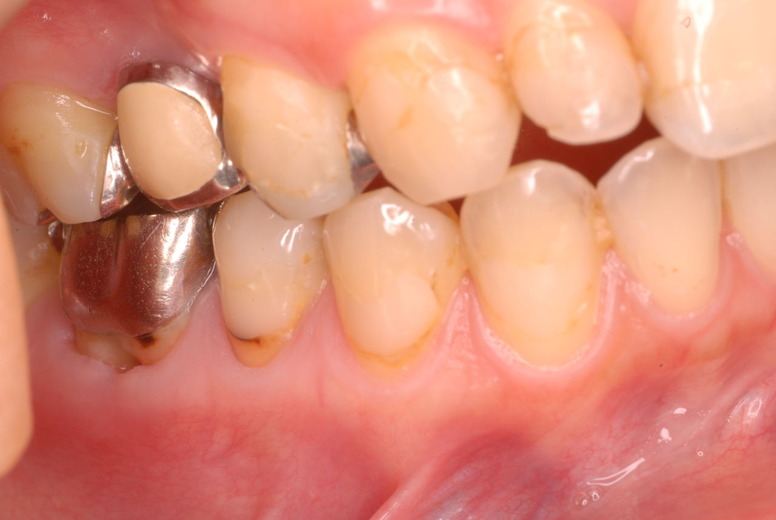

写真左下の親知らずが痛くなり抜歯しました。その後歯茎を除去して虫歯を露出させる処置を二回ほどしています。

レントゲンでは小さいですが、こう言う虫歯が一番怖いのです。

治療の成功率は極めて悪くすぐ再発しやすいのです。

隣の14歳大臼歯がひどい虫歯になり治療不可能になりつつある状態のレントゲン